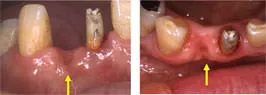

歯槽堤増大術

Before

After

抜歯後の骨吸収によりこのままブリッジを入れてしまうとこの部位だけ歯が長くなってしまい清掃性、審美性共に不良なものになってしまう。組織を移植することにより歯茎の形態を改善させ理想的な形態のブリッジを装着することが出来ました。